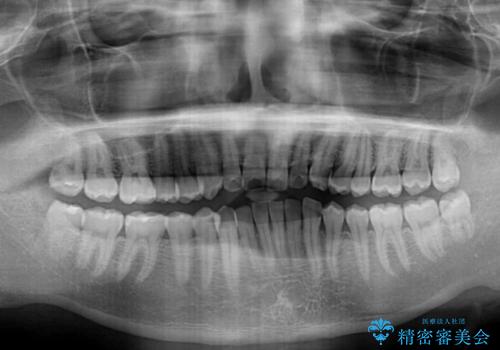

ワイヤー装置での上下前歯の部分矯正

- 上下前歯のデコボコを気にして来院された患者様です。

口元の突出感や奥歯の咬み合わせに問題がなかったため、インビザラインの廉価版パッケージを用いるか上下ワイヤー装置での部分矯正を提案しました。

部分矯正は咬み合わせが不安定になったり、スペースができてしまったりと、適用となる患者様は極めて限られますが、こちらの方はスムーズに治療を終えることができました。